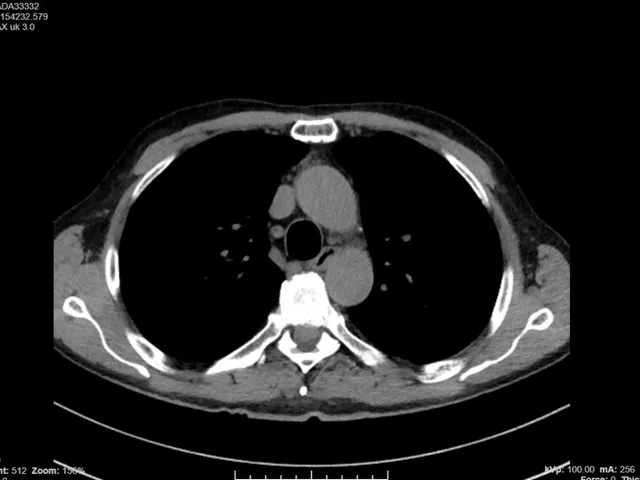

This online HRCT course, facilitated by expert thoracic radiologist Prof. Pierre-Yves Brillet, covers key topics related to pattern recognition in interstitial lung diseases (ILDs) of the lung.

This online HRCT course provides medium and advanced knowledge on high-resolution computed tomography of the Chest through lectures, individual case readings and group case discussions.

• To increase knowledge and ability to identify patterns and diagnose interstitial lung diseases (ILDs) and granulomatous disease

• Identifying fibrosis like UIP/IPF and its most common differential diagnoses

• Various lectures on imaging features of Interstitial Lung Diseases

• Individual case reading and interpretation on provided cases

• Group case discussion of the selected cases